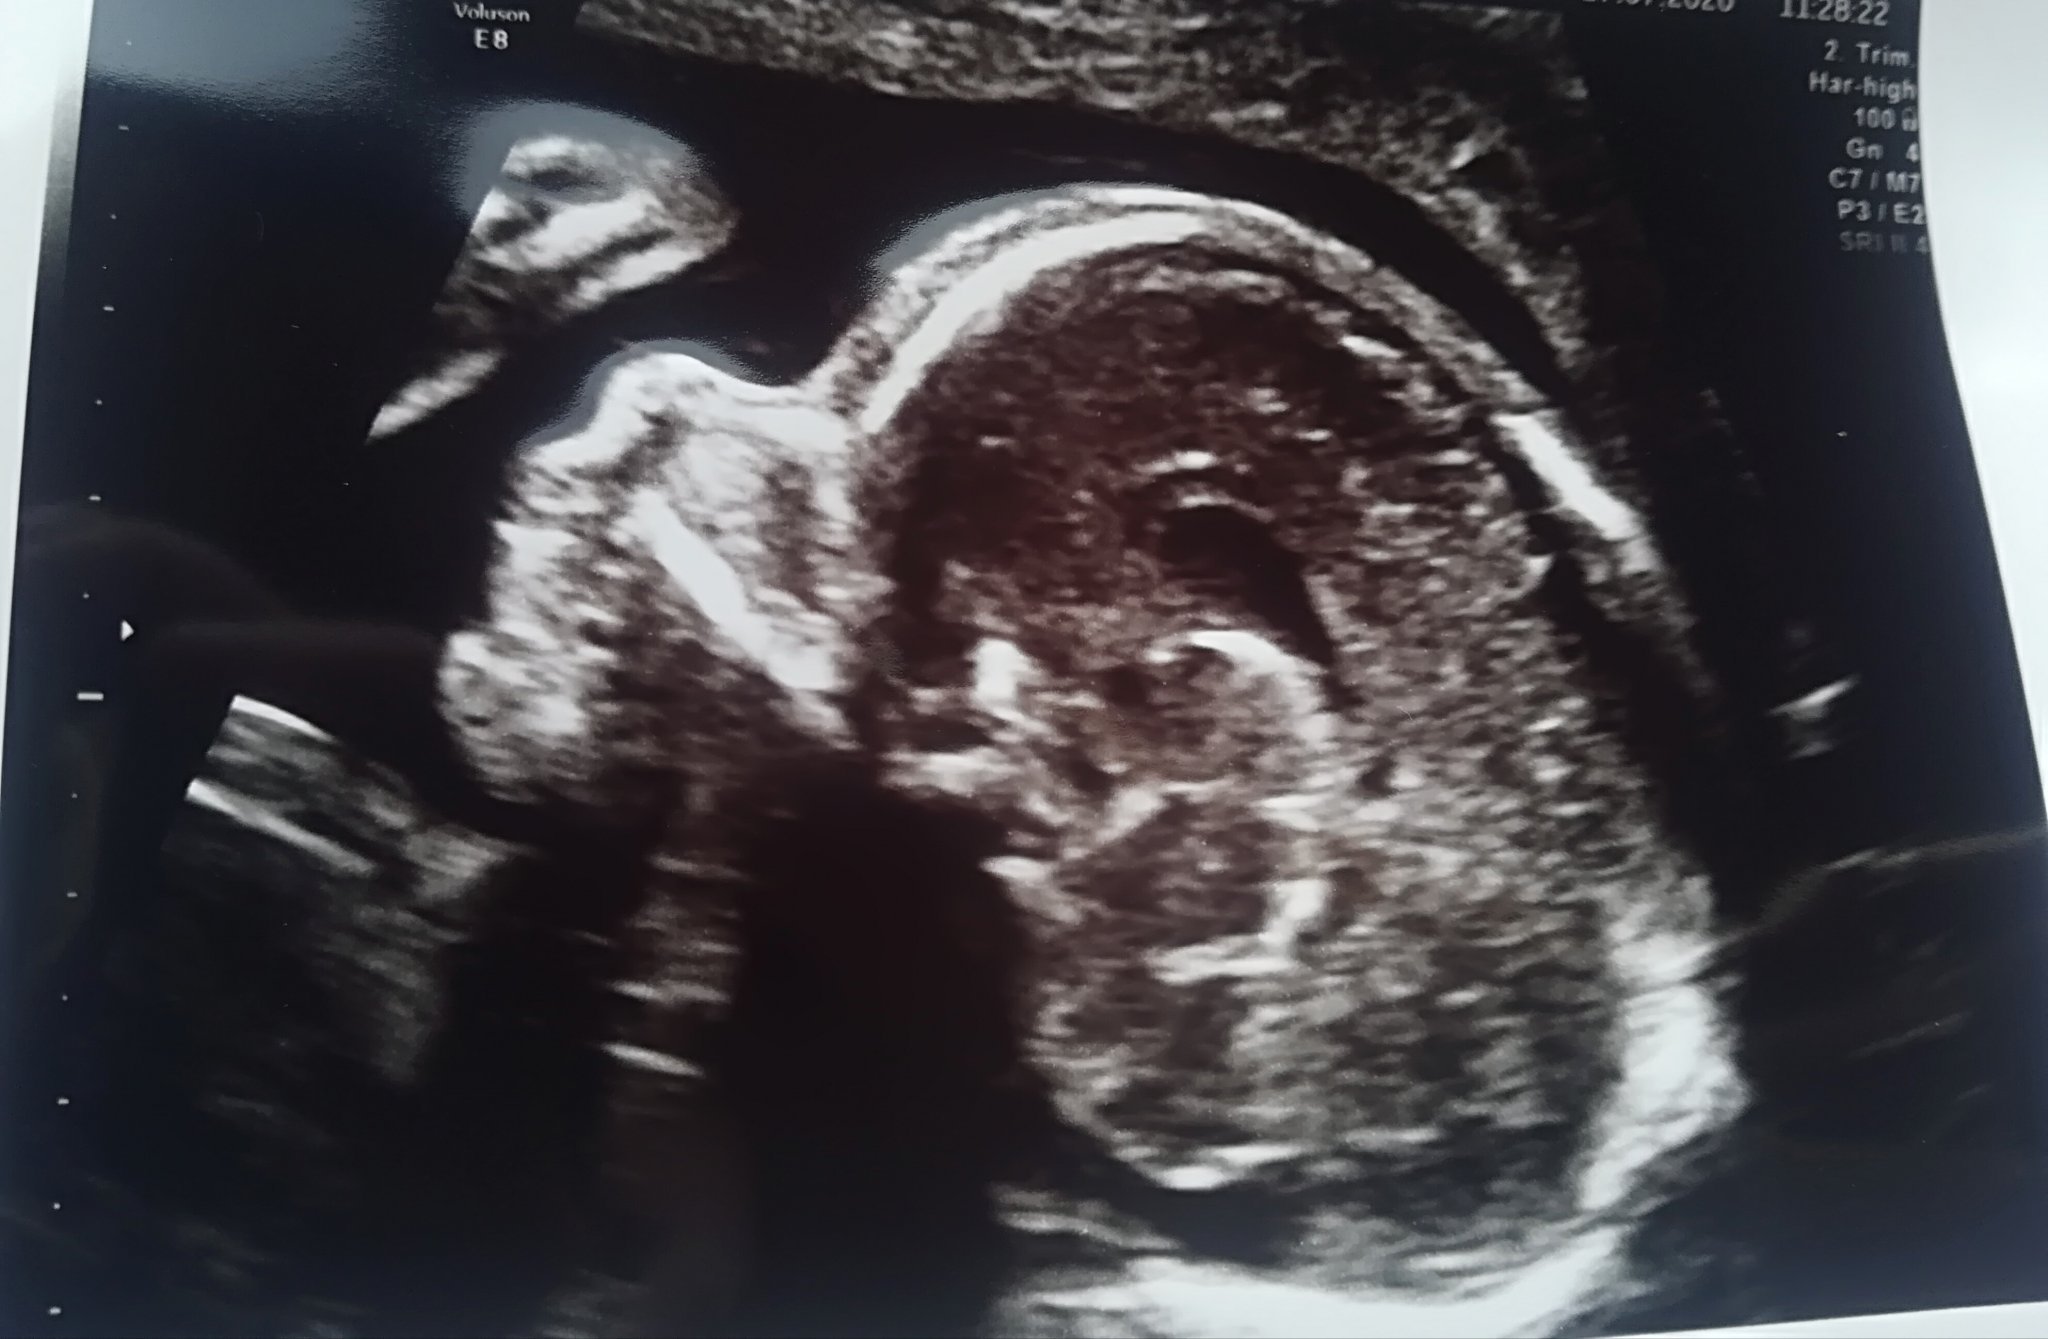

Основните теми в дискусията включват пожелания за успешни бременности, споделяне на лични преживявания и препоръки за лечение на различни здравословни проблеми като уреаплазма и дефицит на витамини. Форумът също обсъжда методи за забременяване, резултати от лечението и подкрепа за участниците в процеса на опитваме се да забременеем.

След 1 раждане, 2 миседа и 1 БХ, вече съм 5та бременност... Започвам с терапията и многото прегледи.